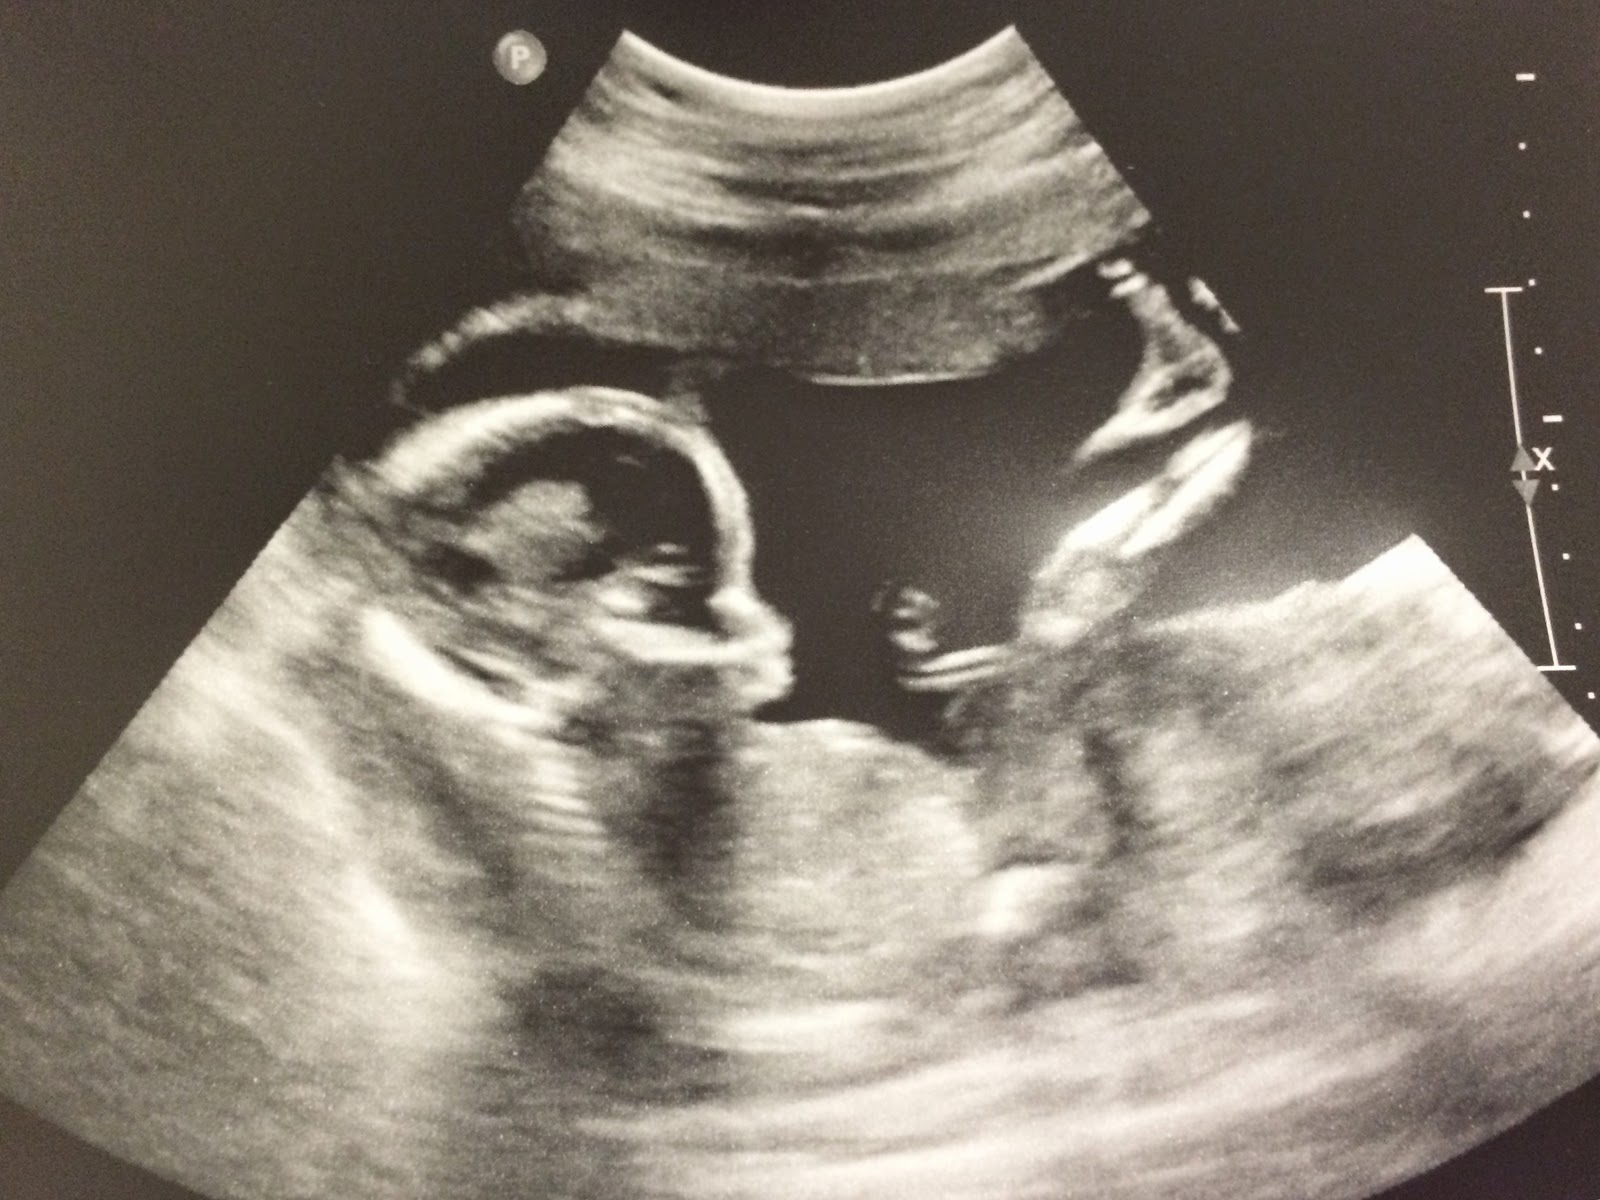

Emme is born 11:24 am

I tossed and turned all night knowing that we would be a family of 4 before the day ended. They were inducing me at 9am, at 39 weeks and 5 days, 2 days short of 40 weeks. Nathan had arrived on his own, 4 days past his due date. Emme had decided not to turn around and was therefore going to be pulled out via c-section. I was extremely nervous about the c-section, although many mothers had told me that it would be done sooner than natural birth and it would be less painful. I remembered how painful it had been when Nathan was born, how much I had pushed to bring my little prince out, so I could definitely do without much pain during the labor this time around, given that I had no choice. We drove to my mothers house and dropped off Nathan. We told him we were going to go get his little sister and that soon enough he would come to the hospital and meet her. We reminded him that Emme was bringing him a gift, and that he would be so excited to see it. I remember embracing him so tightly.

We checked into the hospital where we were soon admitted into our room. Soon enough nurses began to come in and out of the room, setting up my IV and prepping me for major surgery. I remember the nice older nurse having difficulty with my IV. She kept apologizing while I cried. At the moment I wasn’t sure why I cried. She kept saying sorry and I kept saying I was ok; I was simply nervous since I had never had a c-section. Eric held my hand telling me we were going to be ok and to think of the beautiful baby we would soon hold in our arms. We even took a picture of ourselves right before they rolled me away. Eric kept telling me not to be afraid but my heart was heavy. I was scared.

They rolled me into the operating room where there were 8 people, all for different jobs, prepared for an emergency and if anything would go wrong with either me or the baby. They brought the anesthesiologist and began the process of numbing me. My tears kept rolling down my cheeks and I remember the doctor telling me that everything was going to be fine and it would be over so quickly. I nodded my head and continued to stay still, as they injected the needle in my back. Slowly I felt the cold liquid run through my back and I laid down.

I felt the pressure of the incision as they cut through five layers of tissue. One by one they got closer to my little girl. I felt something removed and I knew she was no longer inside me but I heard no cry. I heard a heavy silence. I asked how much she weight and why she wasn’t crying. The doctor quickly responded saying that sometimes they had to do a couple extra steps to let the baby know it was outside. Seconds later I heard her sweet cry. My heart was at ease and my doctors began to sow me right up as they talked about some mediocre hospital administration issues. Then they rolled Emme right pass me, stopping very quickly so I could see her, we locked eyes and it was then I saw her blue eyes and how much she looked like Nathan. I smiled as they explained they needed to take her for some extra check ups to make sure everything was ok. Eric left with her.